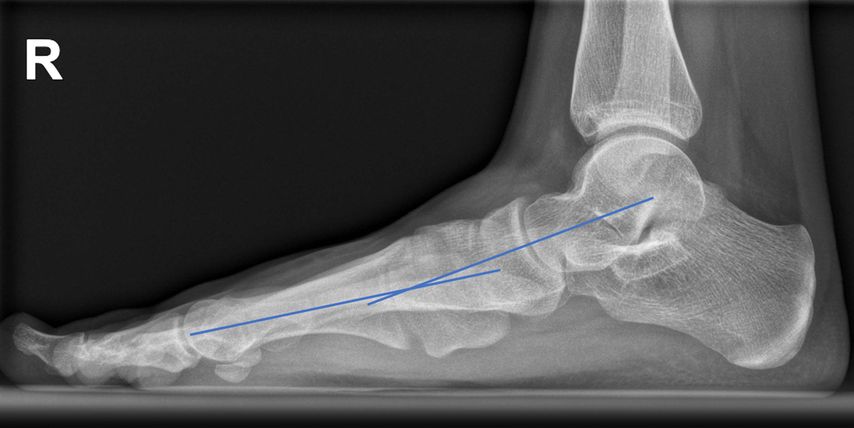

Abb. 1: Präoperativ: blaue Linie = Talus-MT1-Winkel; gebogene Linien: „talar head uncoverage“

Die Röntgenaufnahmen des Fußes und des oberen Sprunggelenks im dorsoplantaren (d.p.) und seitlichen Strahlengang erfolgen am belasteten Bein, um die Fehlstellung in ihrem vollen Ausmaß zu erfassen. Zusätzlich wird für die nativradiologische Abklärung eine Rückfußaufnahme nach Saltzman durchgeführt, in der die Valgisierung des Fersenbeines gegenüber der Tibiaachse dargestellt wird.

Auf der seitlichen Aufnahme sind die Abflachung des Längsgewölbes und die Lokalisation der gegebenenfalls vorliegenden Instabilität der medialen Säule zu erkennen (Talus-Metatarsale1-Winkel = „Meary’s angle“ 0°). Auch ein Metatarsus primus elevatus als Hinweis auf eine Supination des Vorfußes kann vorliegen (Abb. 2).